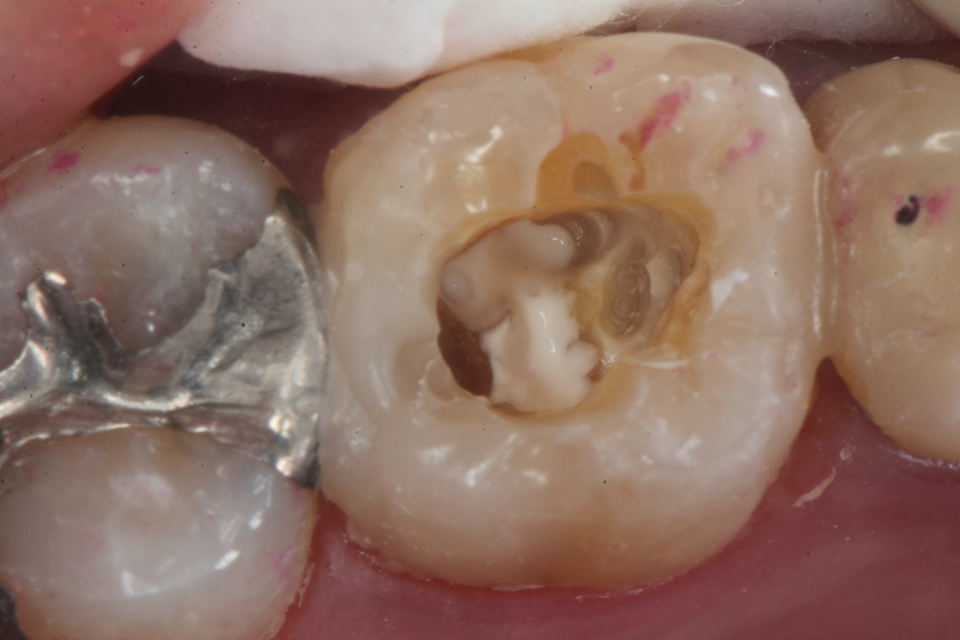

残根上のCR(ダイレクトボンディング)8 2025.11.12

ブリッジ脱離で2次カリエス+Perでグラグ… 2025.11.01

ブリッジ脱離で2次カリエス+Perでグラグ… 2025.10.31